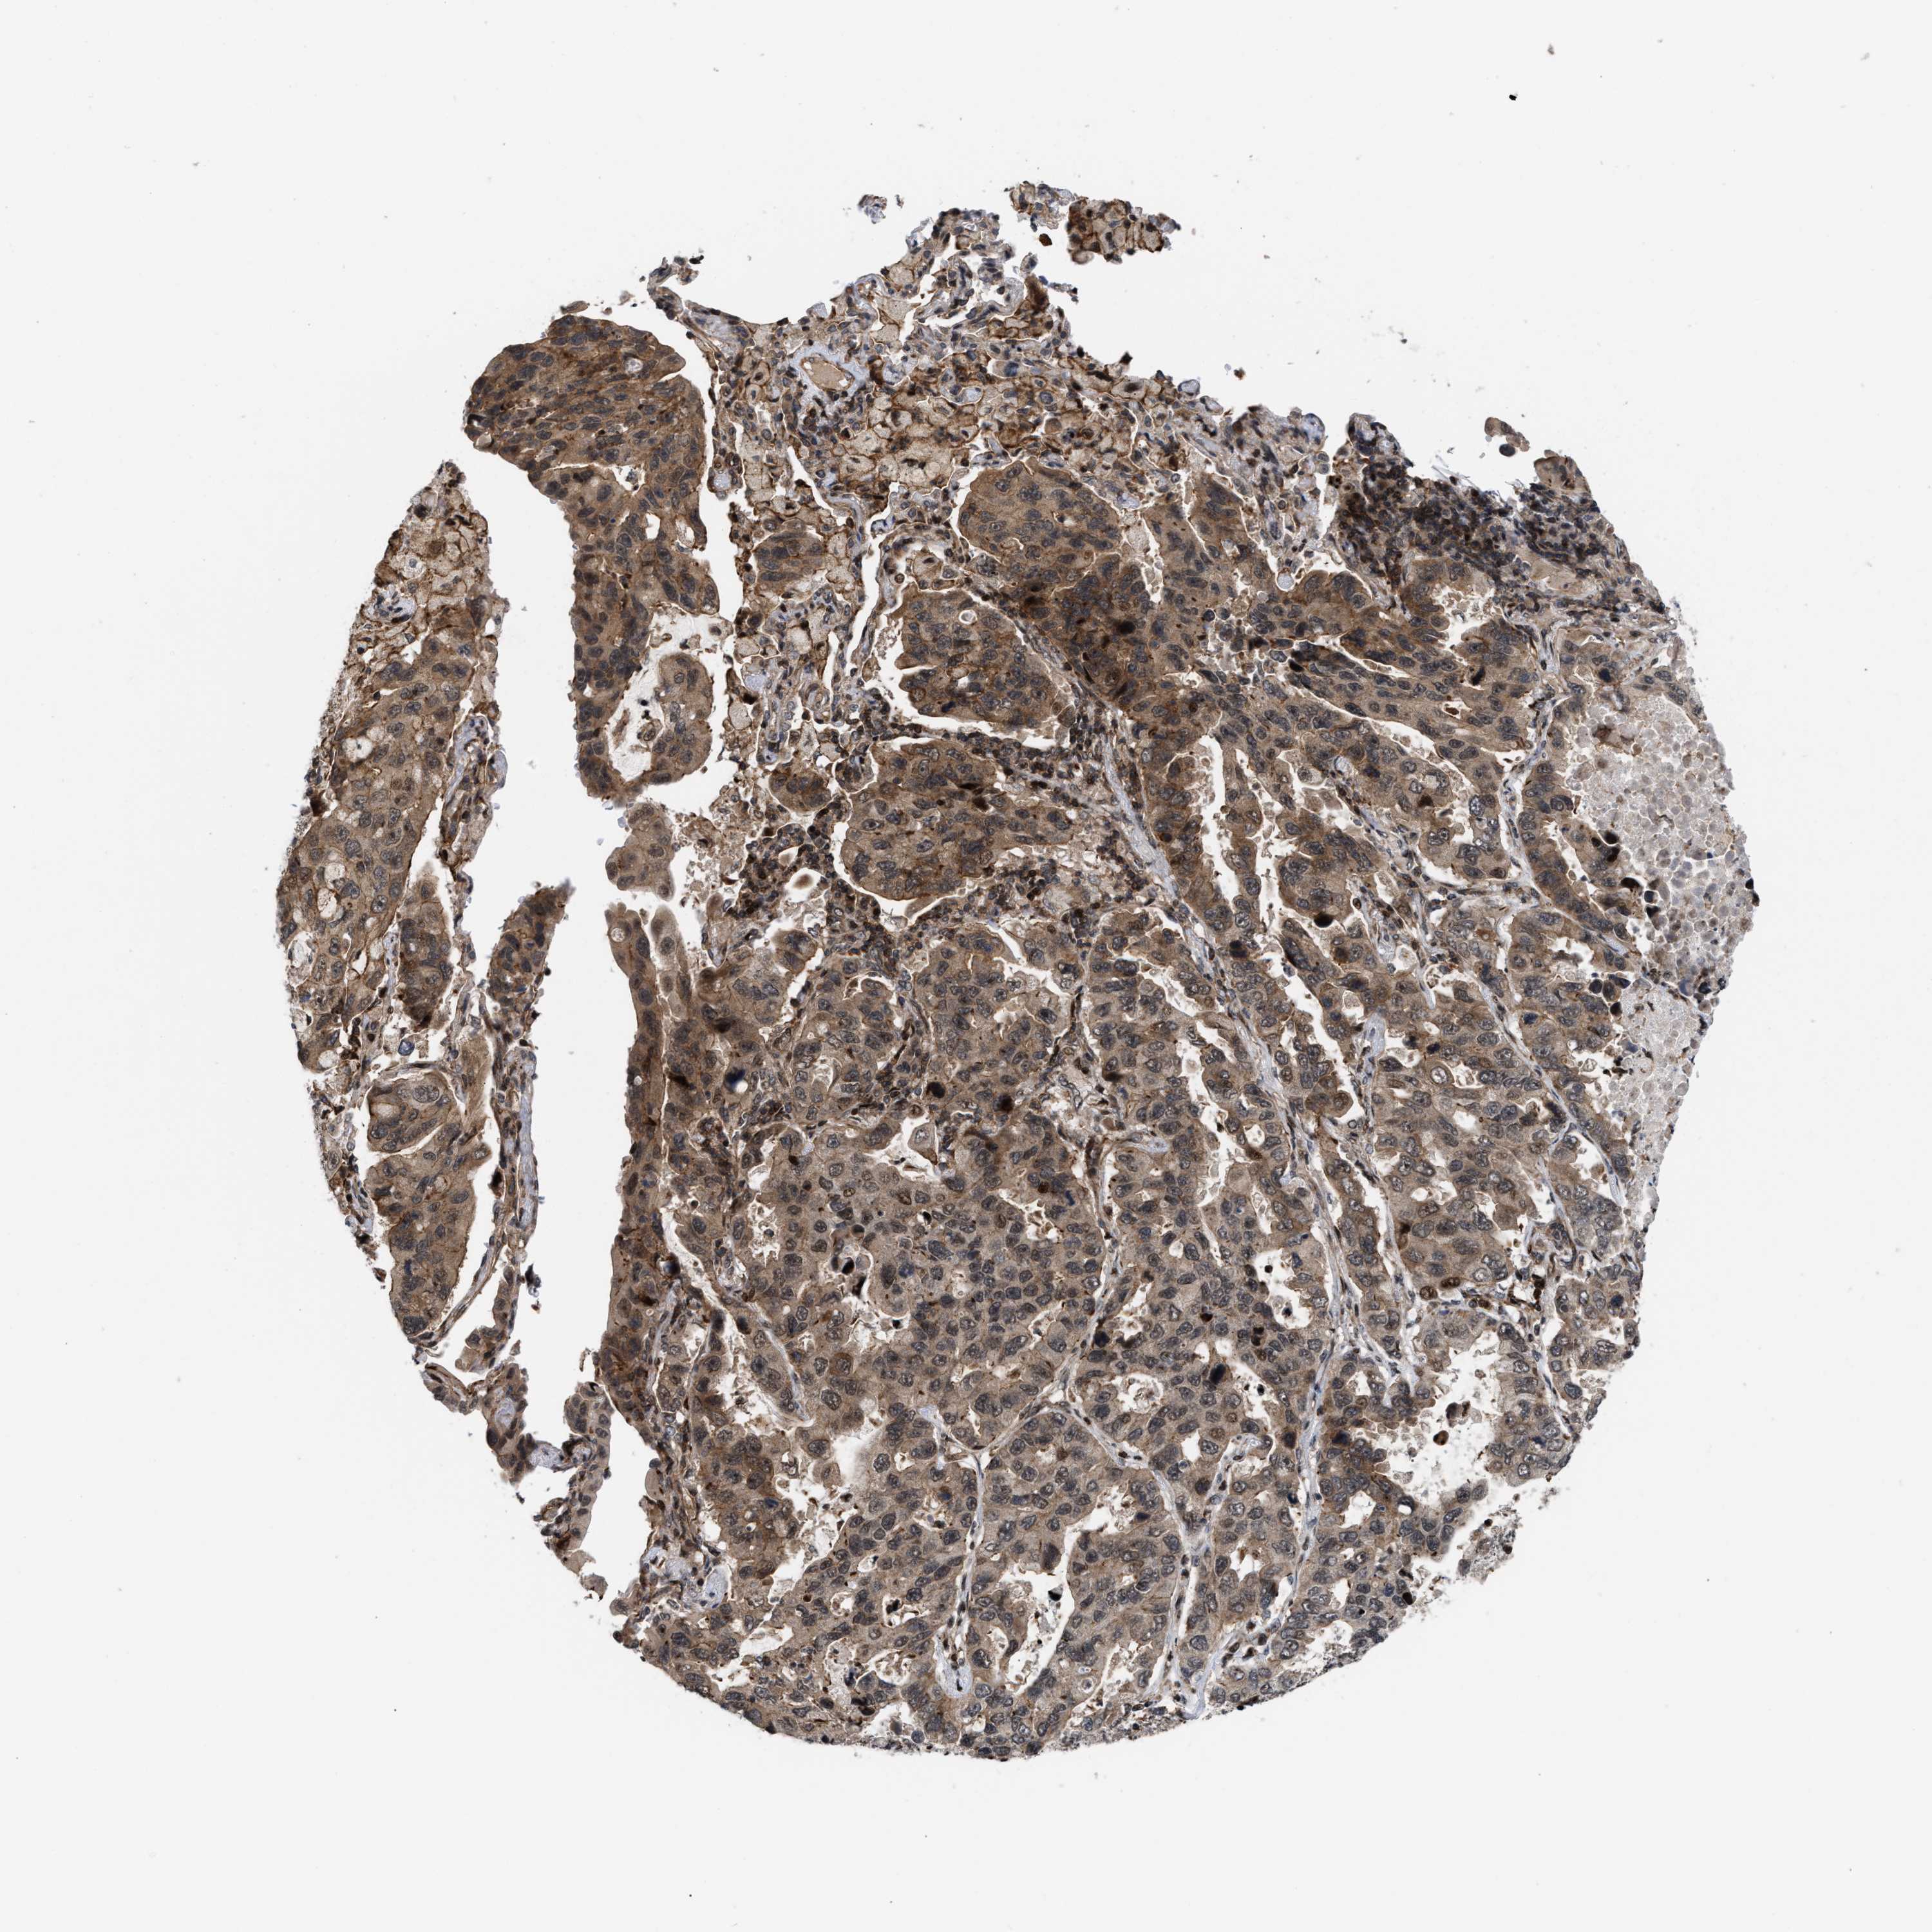

CANCER LUNG CANCER Show tissue menu

LUAD TCGA LUAD VALIDATION LUSC TCGA LUSC VALIDATION PROTEIN LUAD CPTAC PROTEIN LUSC CPTAC PROTEIN EXPRESSION